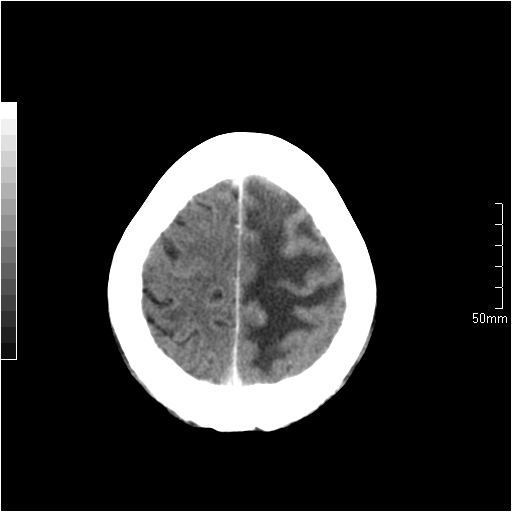

以下是引用天南地北在2007-6-25 12:39:00的发言:[br]有占位效应[br]支持术后复发

以下是引用zjzjr在2007-6-25 12:38:00的发言:[br]左侧复发,右侧转移。